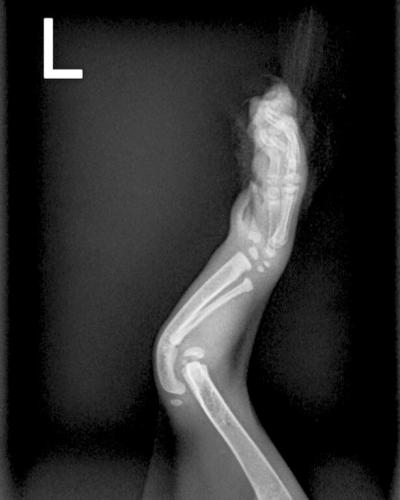

Colt came to the Best Friends Lifesaving Center in Salt Lake City from a nearby shelter with his mom and littermates. The fluffy kittens (all named after baby animals) were about 4 weeks old. Our vet staff learned that Colt was born with front leg deformities. To fully understand his condition, they sent Colt for X-rays and to see an orthopedic specialist.

“Unfortunately, the deformities in his bones were too severe for surgery to correct,” says Dr. Megan McCarthy, Best Friends veterinarian. Walking on his front elbows would be Colt’s “normal.” It doesn’t cause him any pain.